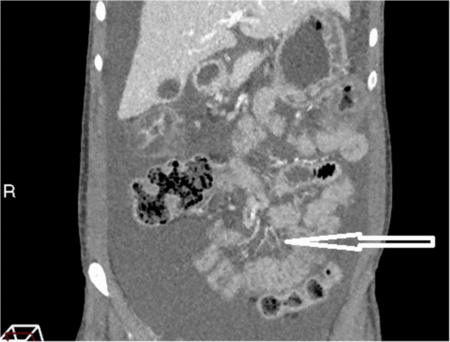

Una Manifestación Rara del Dolor Abdominal en el Lupus Eritematoso Sistémico: Un Informe de Caso sobre Enterocolitis Lúpica El lupus…